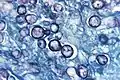

Elle est utilisée pour détecter les organismes fongiques pathogènes dans les tissus tels que Histoplasma capsulatum (agent de l'histoplasmose) ou Pneumocystis jiroveci (anc. P. carinii, agent de la pneumocystose)[2].

La coloration donne un aspect brun à noir aux parois cellulaires.

La coloration repose sur la réduction des ions argent, ce qui rend la paroi cellulaire fongique noire. Cela est rendu possible car la paroi cellulaire fongique contient généralement des polysaccharides.

Au cours de la coloration, de l'acide chromique est d'abord utilisé pour oxyder les polysaccharides, ceci générant des aldéhydes. Ensuite, la solution alcaline d'ions argent et de méthénamine de Grocott est appliquée, ce qui réduit les ions Ag+ en argent métallique amorphe coloré en noir.

La réaction de réduction par la paroi cellulaire fongique est souvent connue sous le nom de réaction argentaffine[3].